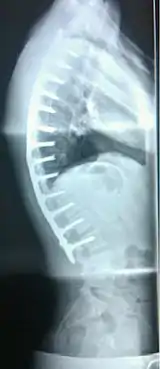

Scheuermann's disease

Scheuermann's disease is a self-limiting skeletal disorder of childhood. Scheuermann's disease describes a condition where the vertebrae grow unevenly with respect to the sagittal plane; that is, the posterior angle is often greater than the anterior. This uneven growth results in the signature "wedging" shape of the vertebrae, causing kyphosis. It is named after Danish surgeon Holger Scheuermann.[3][4][5]

| Scheuermann's disease on lateral Xray of the T spine | |

Diagnosis is typically by medical imaging. The degree of kyphosis can be measured by Cobb's angle and sagittal balance.